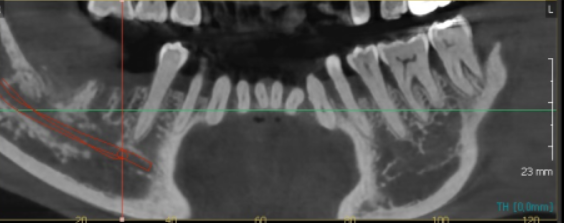

23.12.30

그리고 또 한달이 지나

ct를 한번 보실까요~?

발치 후 뼈이식 4개월 뒤입니다.

아직도 웅덩이 진 모습이 보이시죠~?

완전하지는 않지만

이정도면 ct에서 뼈가 남아있는 부분으로

임플란트 수술이 가능했습니다.

23.11.16

기존에 이 흔들림 자리에 임플란트를 심게되면

뼈가 남아있는 것이 거의 없어

신경선을 건드리게됩니다.

수술 후에 입술 주변 감각이 무뎌지게 되는데요.

신경 손상을 피하기 위해

기존 치아가 있는 앞쪽으로 임플란트를 심었습니다.